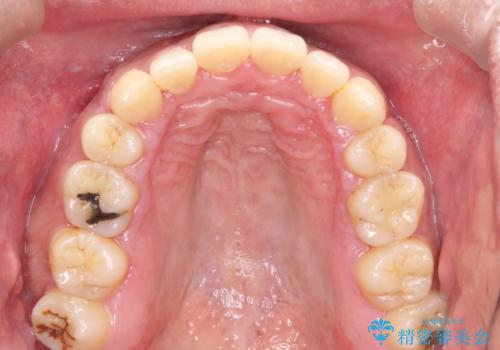

- 出っ歯が気になるとのことで来院されました。

上顎の前から4番目の歯を両側、合計2本抜歯して矯正する計画としました。

目立たない装置がご希望でしたので、上下裏側ワイヤー装置を選択されました。